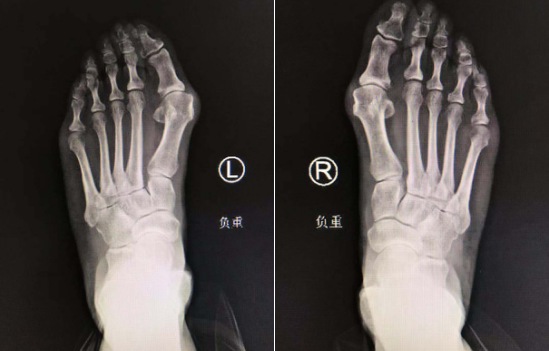

足踝外科曹广超主任接待了孙大姐,给她做了详细检查。孙大姐左足较右足畸形程度更严重些,踇趾都自跖趾关节向外侧偏斜移位,前足变宽,第一跖骨头内侧膨大,踇囊形成,已经是重度拇外翻程度。关节囊的挛缩,肌肉的挛缩,韧带的紧张,造成畸形难以复位。像孙大姐这样,已经出现关节受损、严重跖骨痛、僵硬性畸形的患者,只有通过矫形手术才可以解决足部的畸形和疼痛问题。

曹主任很快安排孙大姐住院,进行各项术前检查,第二天就给孙大姐施行了双足踇外翻矫形手术。

术中,曹广超主任苏省王岩岩医生手术小组依次切除患者左右足增生的踇囊,切除跖骨头骨赘,对第一跖骨做chevron截骨,推挤跖骨下半向外平移,充分松解踇内收肌。手术做得很细致、成功。